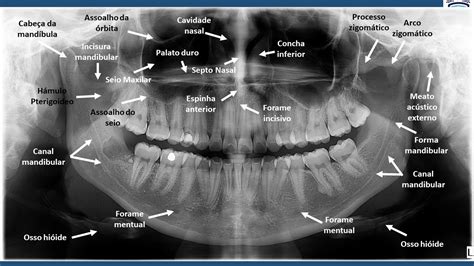

¿Qué es la ortopantomografía dental y para qué sirve? La ortopantomografía dental es una radiografía panorámica que permite obtener una imagen en dos dimensiones de toda la estructura bucal: mandíbula, dientes, encías y huesos maxilares. Es una herramienta diagnóstica fundamental en odontología moderna, utilizada en múltiples tratamientos dentales gracias a su precisión y rapidez.